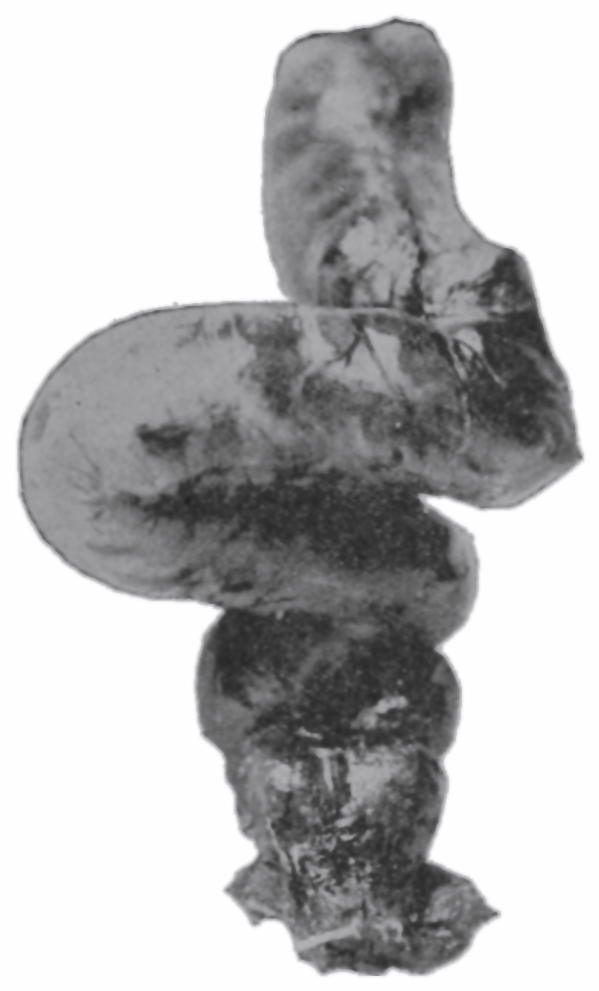

Fig. 20.—Drawing of specimen No. 284 in the Anatomical Museum of the Royal College of Surgeons, London. The dissection was made by Mr. William Pearson. The drawing shows in the lower part of the field behind the rectum the coccyx, in the upper part of the field the pubes.

The fixed anal rectum begins at the levator ani and coccygeus muscles. The levator ani has its origin at the sides of the bodies of the pubic bones, the coccygeus at the spines of the ischii, and the levator ani has additional origin from the fascia and bony parts on a line between these two points. The fibers of these muscles are directed downward and inward to the fixed anal rectum; many fibers are blended into the contiguous structures of the pelvic floor. The coccygeolevator muscles may be compared to an opened slat-fan, the apex having its place at the anus, and its long border representing the line of origin of the muscles, Fig. 19. The ental sphincter ani muscle, situated a few lines below the levator ani, is made up of an aggregation of the fibers of the circular non-striated muscular intestinal coat, Fig. 20. The ectal sphincter ani striated muscle is situated immediately beneath the external skin. It serves the present occasion to describe the ectal sphincter of the male as a loop of muscle thrown about the terminal end of the rectum and hitched to the terminal bone of the coccyx, and in the female as a longer loop of muscle twisted upon itself so as to make a tandem-loop,[56] which, in the form of the figure eight (8), is thrown about the vagina and terminal end of the rectum.